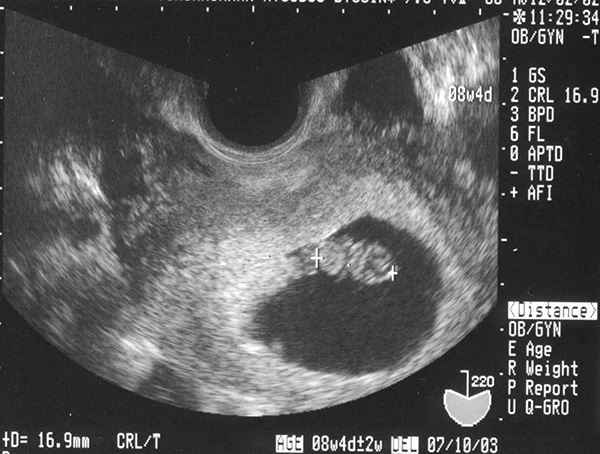

– GSD (Kích thước túi ối): Chỉ số GSD được xác định vào những tuần đầu của thai kỳ, lúc thai nhi chưa hình thành hết các cơ quan, bộ phận cơ thể. Lúc này, chỉ số GSD là 14-25mm

– CRL (Chiều dài đầu mông): Vào thời điểm thai 6 tuần thì chỉ số này bình thường là 4-7mm